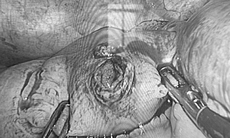

Huyết khối được các bác sĩ lấy ra thành công, khôi phục dòng chảy mạch máu.

Cánh tay phải bệnh nhân sau khi được can thiệp hút huyết khối.